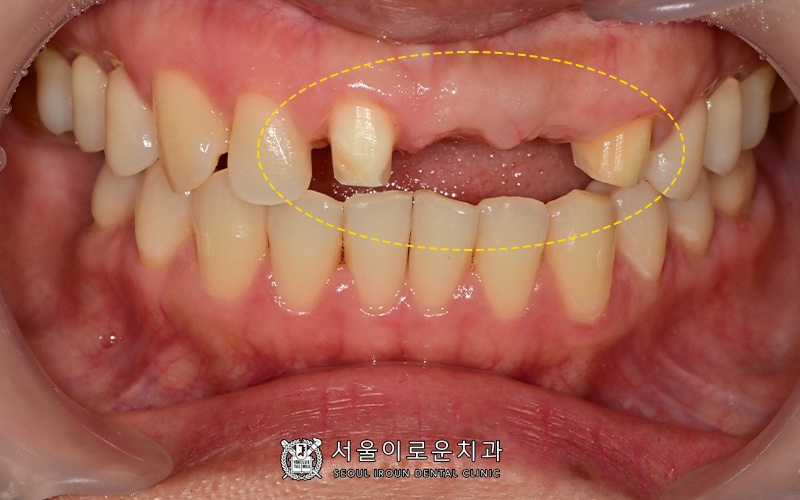

이제 보철(bridge)를 씌우면

치료가 마무리 되는데요~!

보철을 씌우기 전,

브릿지를 연결할 앞에 치아의 인접치 사이에도

충치가 있는 것을 발견했습니다.

보철을 씌우고 나면,

치아사이가 메꿔지기 때문에

충치를 발견하기도 어렵고

치료또한 어려운데요.

나중에 충치치료를 위해

브릿지를 제거해야 할 수도 있기 때문에

발견한 것이 천만다행이었습니다 👍🏻

충치가 심하지 않아, 우식부위를 삭제한 뒤

레진충전을 통해 치료를 바로 진행하였습니다 😀

환.자분도 거울을 계속 보고 싶으시다며

브릿지 모양과 색상에

만족하셨던 치료 마무리 사진입니다~!

어떤 것이 본래치아이고

보철인지 구분이 가시나요~??

기존 치아색상과 자연스러우면서

모양과 치아 길이까지 비슷할 수 있도록

디테일까지 신경쓰는 서울이로운입니다.👍🏻